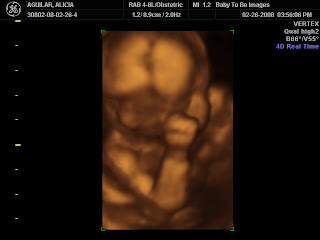

It was amazing to see how much he had grown in just 7 weeks. I'd like to share some pics (the name on the photos is the u/s tech because she wanted to use some of our photos for their marketing materials and this way, it protects our identity):

Our beautiful boy touching his face

It's loud in here, Mommy!